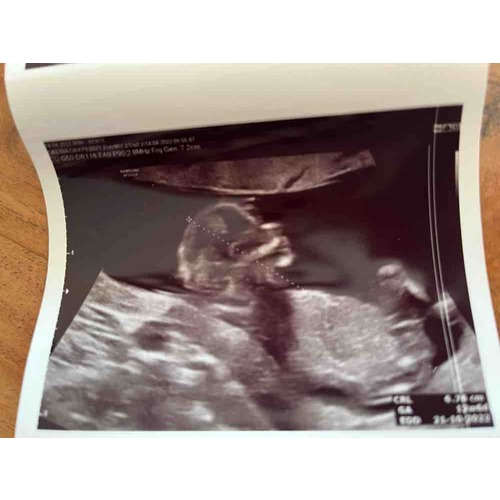

Foto 1: 13+1 week